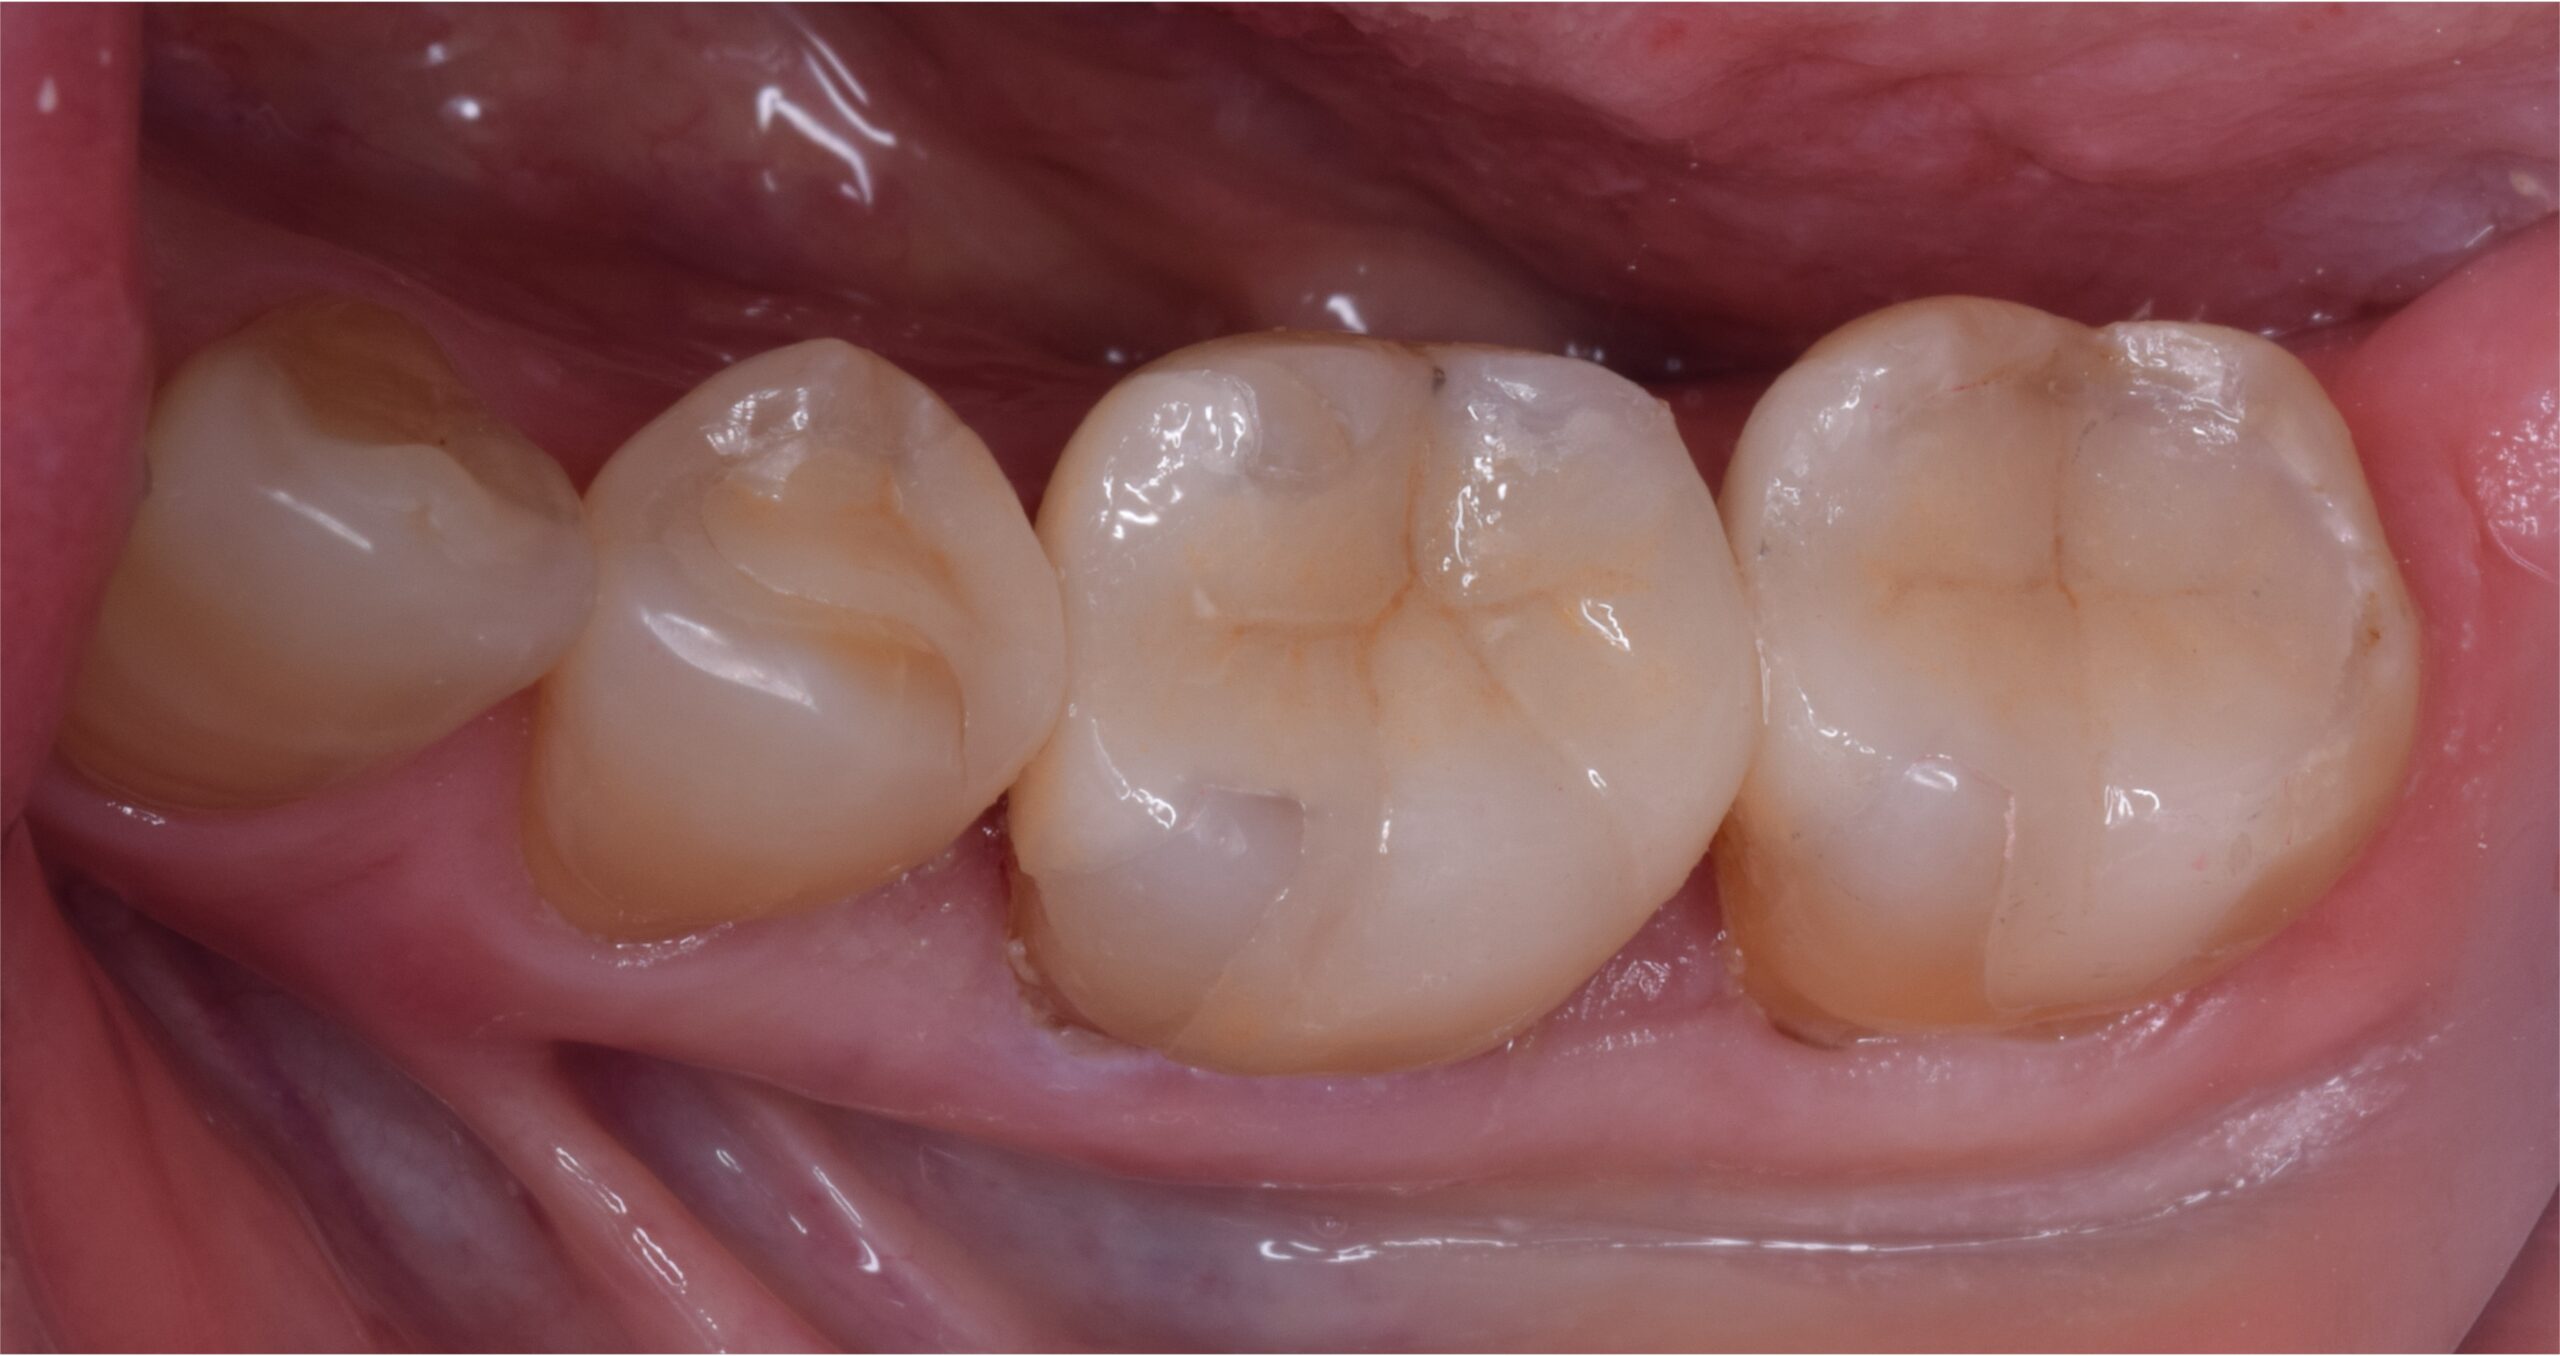

治療後

| 主訴 | 検診してほしい 銀歯の下が虫歯になっていたため治療 |

| 治療内容 | 虫歯治療、セラミックブリッジ治療 |